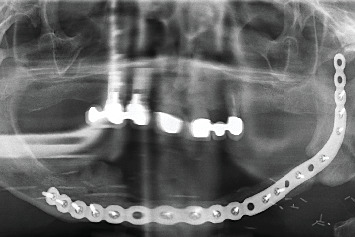

口腔扁平苔藓患者有时会发展为恶性过程,发展为口腔鳞状细胞癌或其他类型的癌症。密切监测病变和早期诊断对提高患者生存率非常重要。一旦进行了癌症治疗,除了解决美学后遗症外,恢复咀嚼和发音功能的治疗选择也很重要。在目前的临床病例中,我们展示了一位接受治疗并随访了很长一段时间的患者,她的癌症和随后的种植体康复。

Patients with oral lichen planus can sometimes develop malignancy of the process and develop oral squamous cell carcinoma or another type of cancer. Close monitoring of the lesions and early diagnosis is important to increase patient survival. Once cancer treatment has been performed, the therapeutic options for restoring masticatory and phonatory function, in addition to resolving the aesthetic sequelae, are important. In the present clinical case, we show a patient who was treated and followed over a long period of time for both her carcinoma and her subsequent rehabilitation with implants.